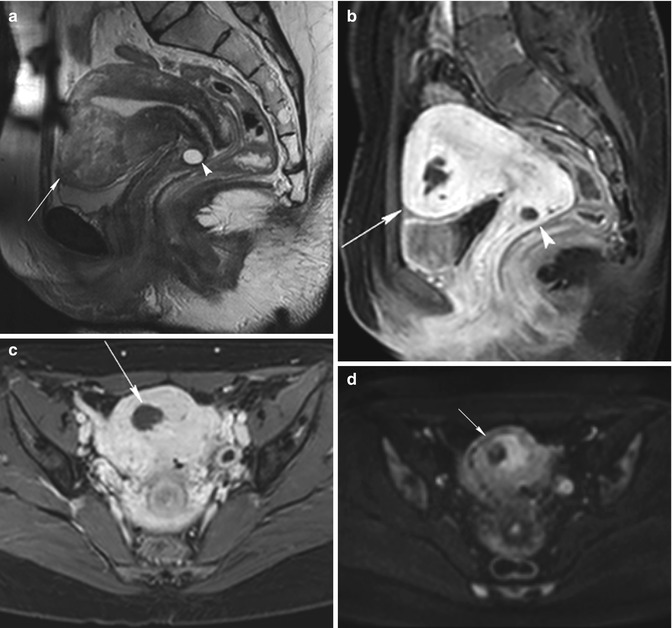

MRI pelvis of a large posterior wall fibroid with cystic degeneration …

MR imaging of atypical fibroids

Additional pathologies found during uterine fibroid MRI screening. a …